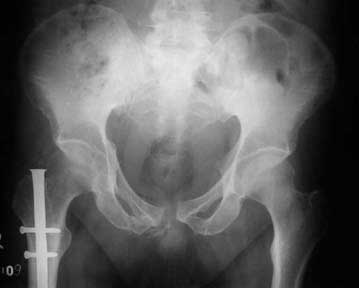

Here are the post op pictures.

I would welcome comments and criticisms. I have a couple of questions to the list: i) How often do you see Rhabdomyolysis (Old term - crush syndrome) ? We have been seeing it on and off. ii) One of the list members suggested using fracture table and traction. I did the femur in lateral positon without traction. How safe is it to use fracture table with perineal post in the presence of pubic symphysis diastasis?

To recap: Middle aged male patient on whom a heavy log fell and sustained injury. Had pelvic ring disruption with fracture femur. Ext fix of pelvis and interlocking nailing of femur done. Developed compartment syndrome thigh and had fasciotomy. Went on to rhabdomyolysis and ARDS. Managed with ventillation and alkalinising. Fasciotomy wound later skin grafted.